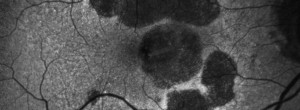

Intra and interobserver agreement in the classification of fundus autofluorescence patterns in geographic atrophy secondary to age-related macular degeneration.

Update on Geographic Atrophy in Age-Related Macular Degeneration.